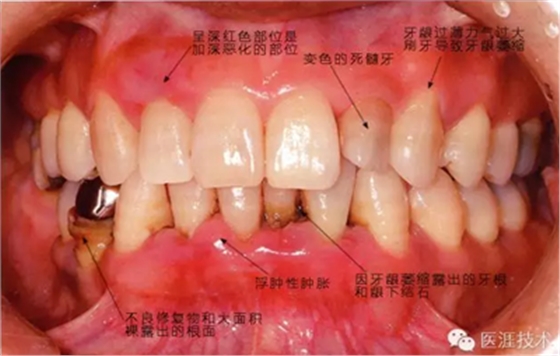

患有牙周病的牙周組織的臨床照片

56歲牙周炎男性的臨床照片

正在服用高血壓藥中的56歲男性。菌斑控制得不好。通過牙周探診,全頜有4~6mm的牙周袋,在X光片中可以看到全頜中度牙槽骨吸收,磨牙處一個地方是重度牙槽骨吸收。通過比較牙周病進展狀態(tài),邊緣部有大范圍浮腫(發(fā)紅、腫脹),和纖維性肥厚。這也可能是服用中的降壓藥的副作用導(dǎo)致的。因為牙齦、牙槽骨比較厚,牙齦呈架子狀。